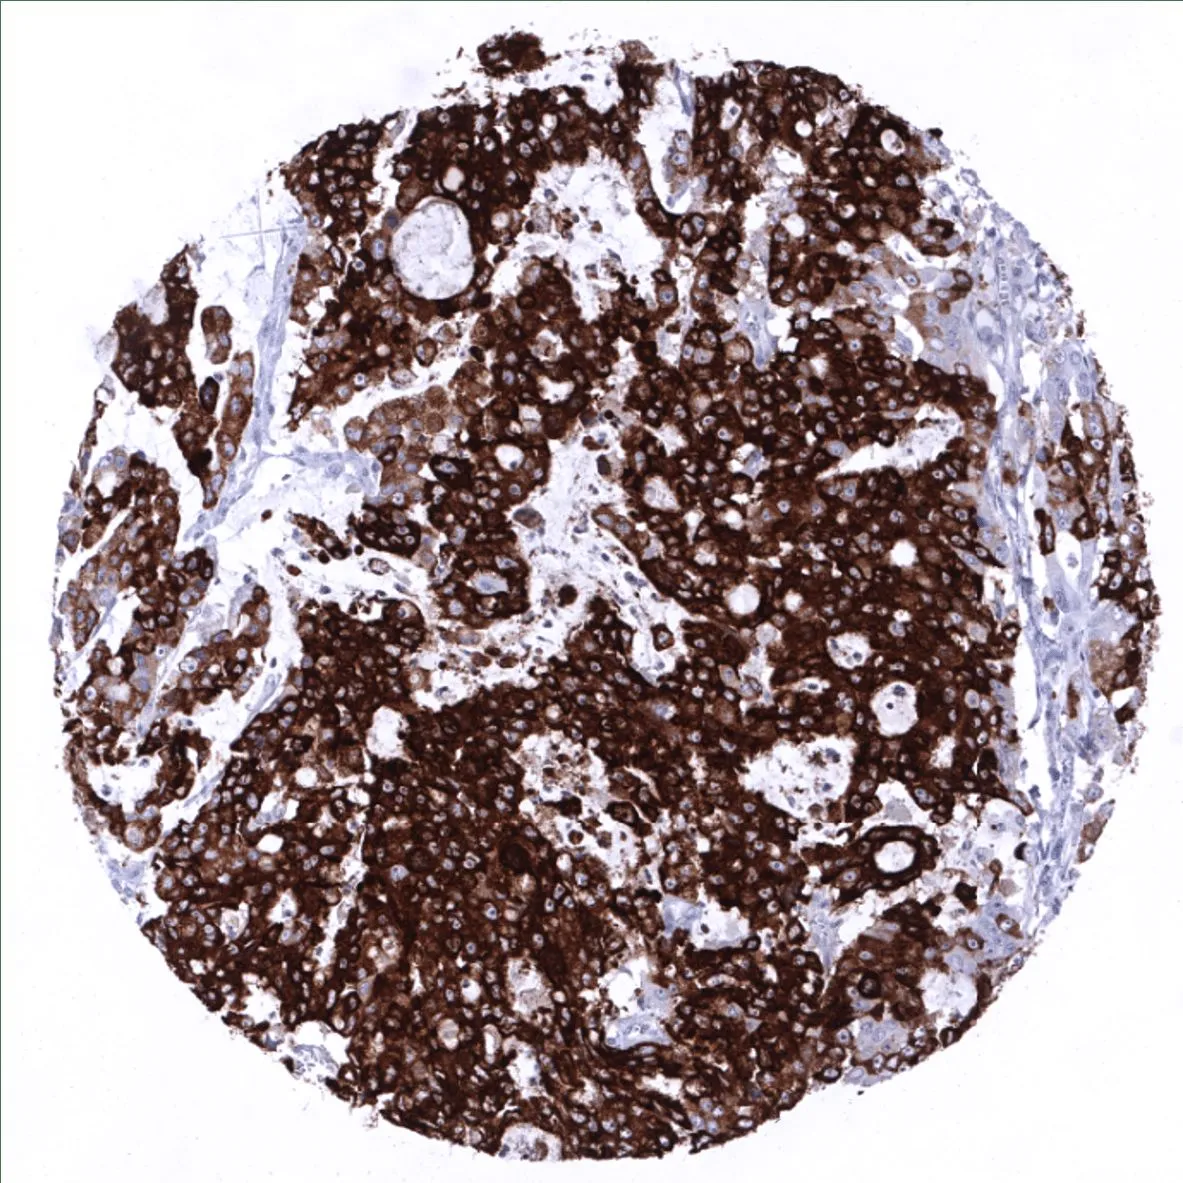

IHC-P analysis of human gastric adenocarcinoma (100% of tumor cells) tissue using GTX04364 Mucin 5AC antibody [MSVA-109M] HistoMAX™.

Strong MUC5AC immunostaining in an adenocarcinoma of the stomach 100% of tumor cells.